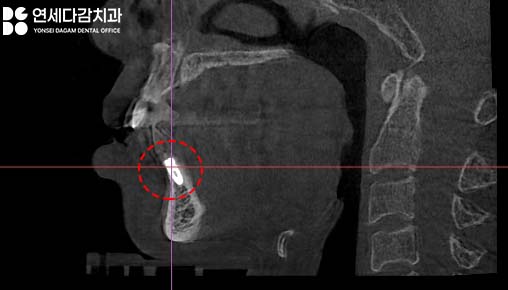

수술 전 CT 촬영

CT촬영을 통해 3차원적으로

구조를 면밀하게 분석하는

과정을 시행합니다.

이 부위는 원래 뼈가 얇은 부위이기도 하고,

염증으로 인한 골 소실로,

더욱 까다로운 환경이

만들어져 있었습니다.

오금역 치과 에서 살펴보고 있는 부위는

하악 앞니 부위이며,

앞서 서문에서 언급했던

임플란트가 까다로운 부위입니다.

뼈가 얇고 심미적으로 중요한

부위이기 때문에

제대로 식립하지 못할 경우

심미적인 결과를 얻기

힘든 경우가 많기 때문이죠.